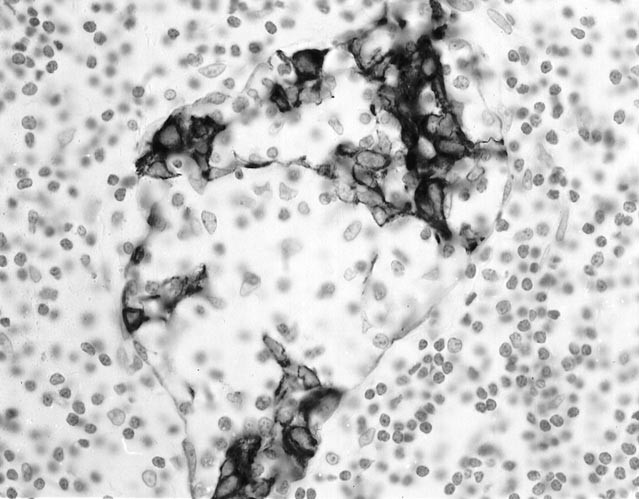

The breast lobules and soft tissue were infiltrated with a malignant population of medium-sized lymphocytes with abundant clear cytoplasm (Figs. 5 and 6). The lobular infiltrate gave the appearance of LE lesions (Fig. 7). The cells in the bronchial biopsy had a similar appearance. No necrosis or vascular invasion was present. The malignant cells were immunoreactive with CD45RB (weak), CD3, CD43, TIA-1, and CD56 (Fig. 8). The cells were negative with CD20, CD45RO, βF1, TCR δ, CD30, CD4, CD8, latent membrane protein for Epstein-Barr virus, and cytokeratin. The diagnosis was revised to NK/T-cell lymphoma. No monoclonal band was found in the IgH or the TCR β or γ assay. The in situ hybridization study for Epstein-Barr virus–encoded RNA was negative.